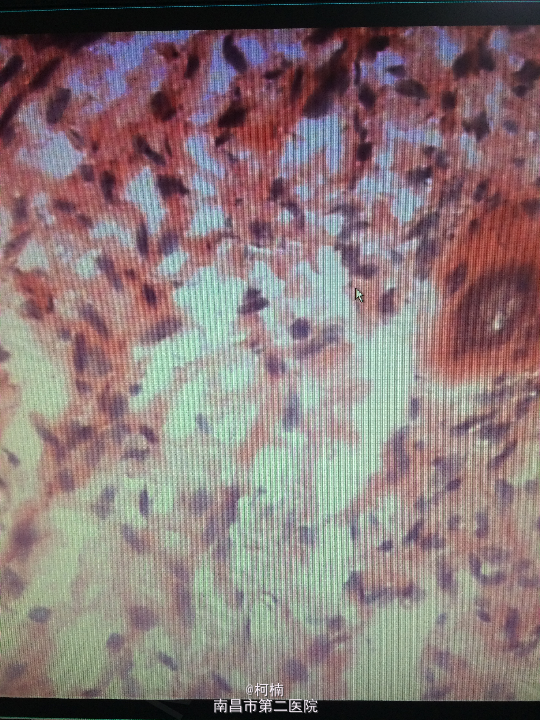

诊断:右侧小脑脑膜瘤 处理:先行介入栓塞肿瘤供血动脉,再行开颅手术治疗,术后予组织病理检查,提示:脑膜瘤

随访:术后患者症状缓解出院 讨论:脑膜瘤(Meningiomas)是起源于脑膜及脑膜间隙的衍生物,发病率占颅内肿瘤的19.2%,居第2位,女性:男性为2:1,发病高峰年龄在45岁,儿童少见。许多无症状脑膜瘤多为偶然发现。多发脑膜瘤偶尔可见,文献中有家族史的报告。50%位于矢状窦旁,另大脑凸面,大脑镰旁者多见,其次为蝶骨嵴、鞍结节、嗅沟、小脑桥脑角与小脑幕等部位,生长在脑室内者很少,也可见于硬膜外。其它部位偶见。手术为其首选的治疗方案。